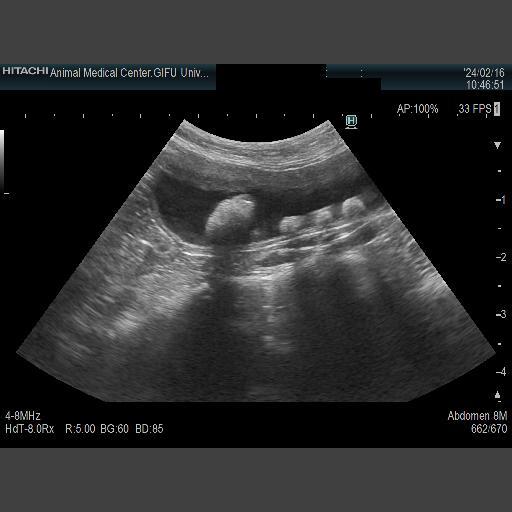

また、この頃から血尿が出るようになり、それも併せて検査していただきました。

原因は恐らくおむつをして生活しているために雑菌が繁殖し、結石も出来てしまっているためとのことでした。

現在では菌の種類も判明し、抗生剤の服用と結石対策の餌を処方していただき治療中です。